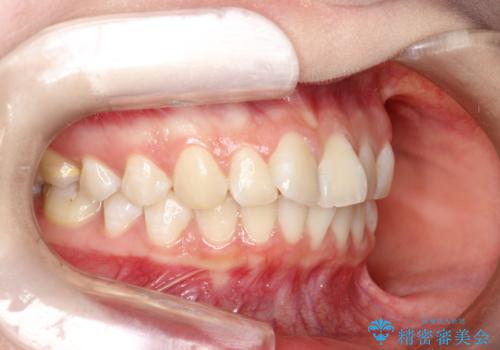

前歯のガタつきを治したい 翼状捻転マウスピース矯正

- 上顎前歯の突出、がたつき(翼状捻転)を主訴に来院されました。当院では総合歯科医療が可能であるため、矯正前処置として虫歯治療・歯周治療、親知らず抜歯を施行しました。その後、非抜歯かつ口元が出ないようなマウスピース治療を行いました。仕事柄、1日の装着時間が短くなってしまう時期もありましたが、患者様と相談しながら問題なく終了しています。